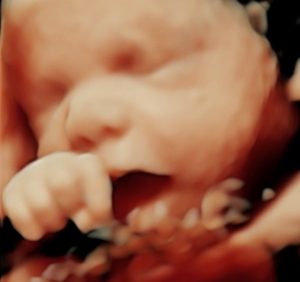

Now Offering The Newest Ultrasound Technology Called HD_Live With All 3D Ultrasound Packages

!New! Advanced 3D From GE Healthcare

!New!HD_Live

Static Image

Virtual Light Source